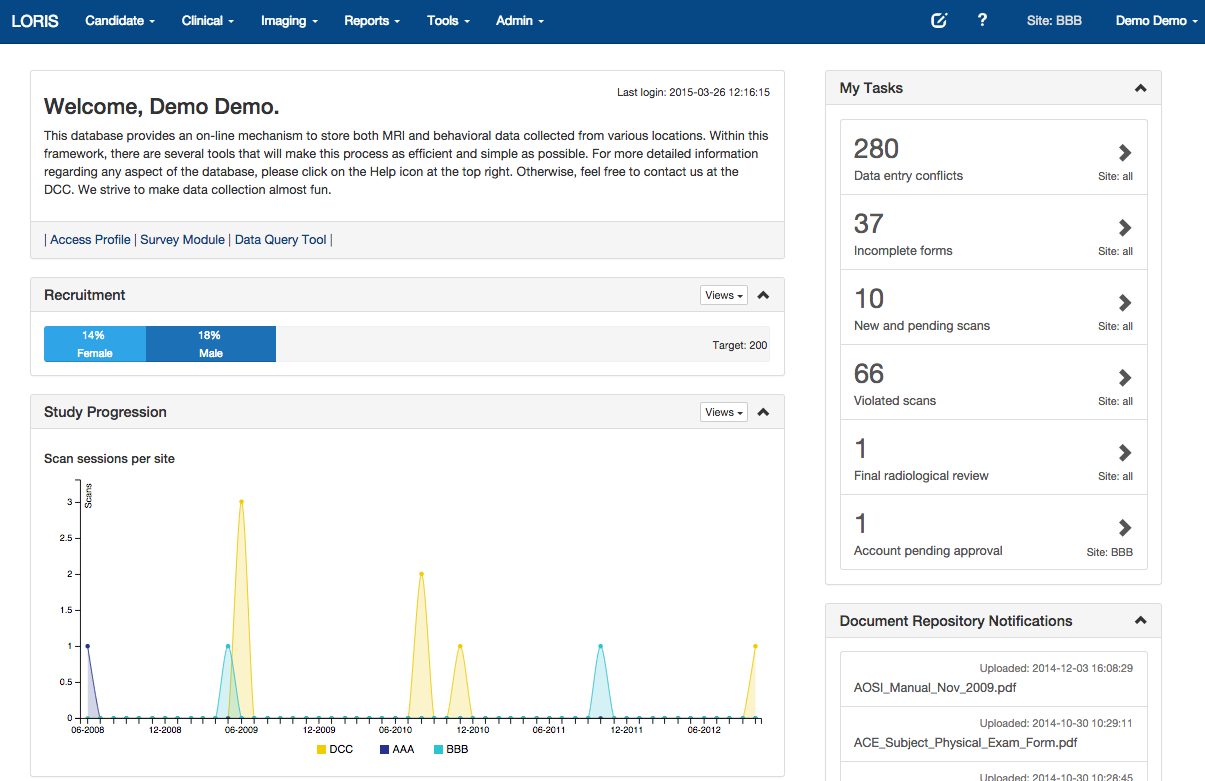

Login

Dashboard

Summary Statistics

LORIS summary statistics

Permissions/User control

List of subjects

Timepoints

Battery of Measures

For list of 400+ instruments: https://sites.google.com/site/lorisinstrumentlist

Psychometric Subject Summary

Psychometric Data Entry

Survey Module

Imaging Browser

Imaging Quality Control